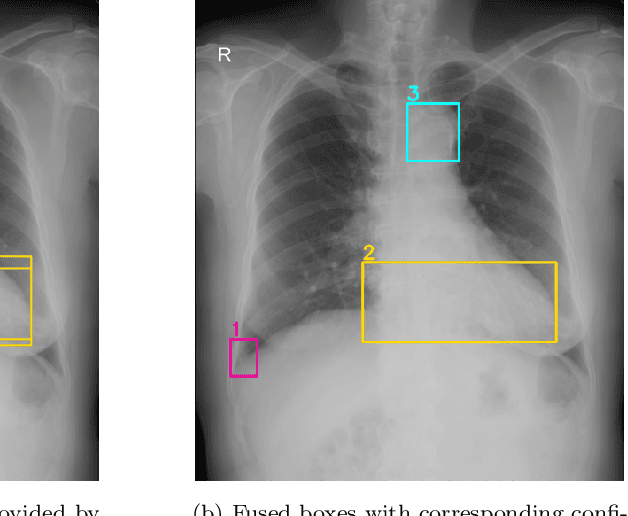

Abstract:Building an accurate computer-aided diagnosis system based on data-driven approaches requires a large amount of high-quality labeled data. In medical imaging analysis, multiple expert annotators often produce subjective estimates about "ground truth labels" during the annotation process, depending on their expertise and experience. As a result, the labeled data may contain a variety of human biases with a high rate of disagreement among annotators, which significantly affect the performance of supervised machine learning algorithms. To tackle this challenge, we propose a simple yet effective approach to combine annotations from multiple radiology experts for training a deep learning-based detector that aims to detect abnormalities on medical scans. The proposed method first estimates the ground truth annotations and confidence scores of training examples. The estimated annotations and their scores are then used to train a deep learning detector with a re-weighted loss function to localize abnormal findings. We conduct an extensive experimental evaluation of the proposed approach on both simulated and real-world medical imaging datasets. The experimental results show that our approach significantly outperforms baseline approaches that do not consider the disagreements among annotators, including methods in which all of the noisy annotations are treated equally as ground truth and the ensemble of different models trained on different label sets provided separately by annotators.